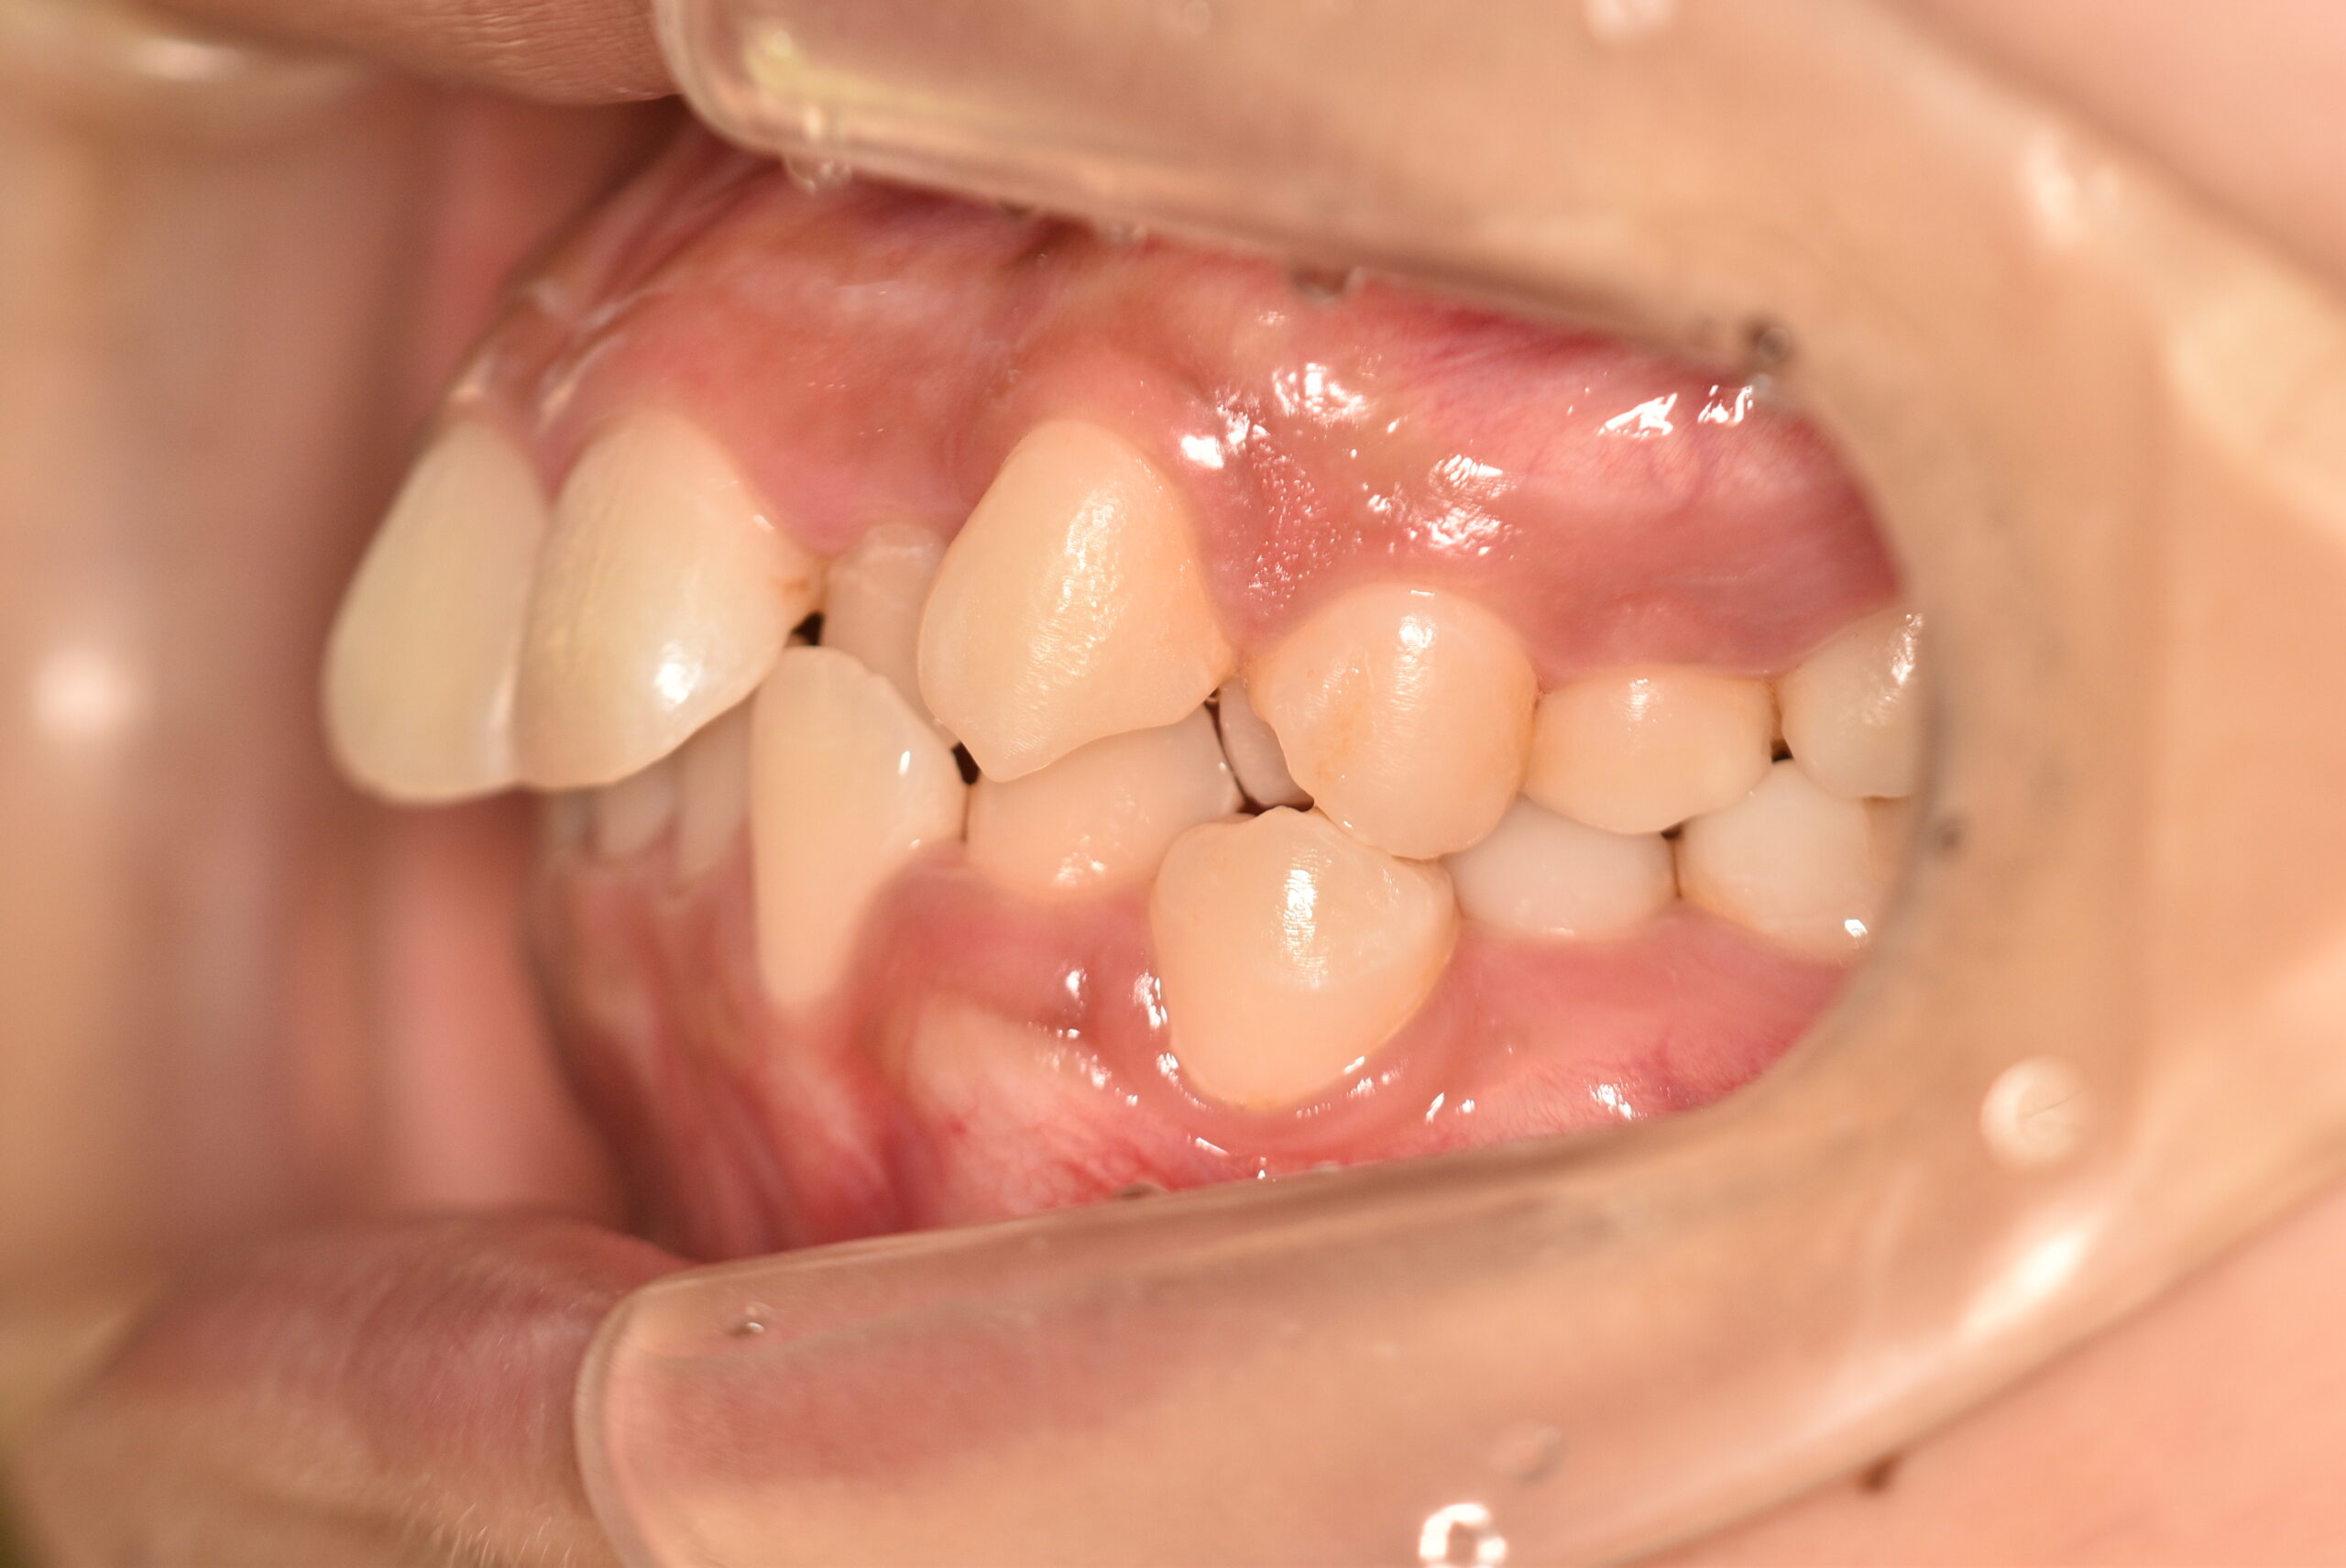

| 治療内容の詳細 | 初診時19歳の女性で、歯のがたつき、かみ合わせを気にされ来院されました。 検査の結果、上顎前歯部叢生を伴うアングルⅡ級1類不正咬合と診断しました。 治療としては、非抜歯の上、セルフライゲーション装置(デーモンシステム)で配列を行いました。 同時に顎間ゴムにて咬合関係の改善を行いました。 治療期間は、2年2ヶ月でした。 |